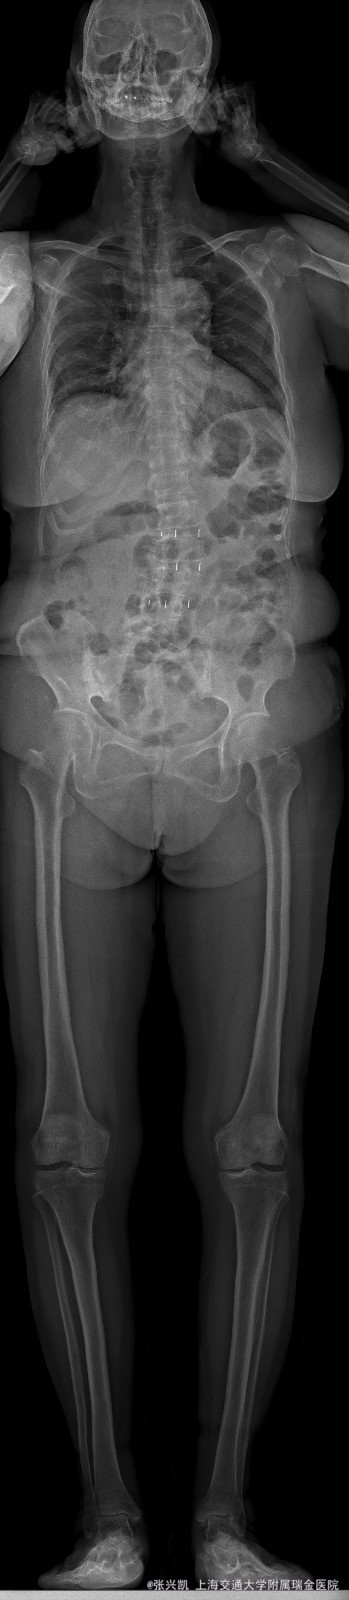

主诉:双下肢麻木7年,腰部酸痛无力 现病史:女性患者,70岁,患者诉腰背无力十几年,约于7年前无明显诱因下出现下肢麻木,站立位加重。后出现腰臀部僵硬,弓背加重,行走距离较短, 不足百米,几年前外院检查诊断为腰椎管狭窄,具体不详。

查体:侧弯畸形,右臀部及右下肢麻木疼痛,腰部活动受限,难以站立。右侧支腿抬高试验50°。双下肢肌力肌张力可。 辅助检查: 磁共振:L1-5,L5-S1腰椎椎间盘突出,腰椎退变,腰椎侧弯

诊断: 腰椎侧弯,腰椎间盘突出 治疗:1期微创侧路椎体融合术+2期 微创后路经皮内固定术

患者侧路微创术后神经压迫症状减轻,腰椎矢状位及冠状位腰椎力线得到改善,戴支具术后可早期下床活动,术后2周后行后路固定手术。